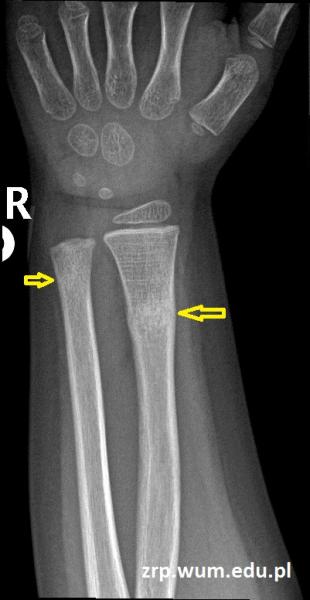

3-latek po urazie przedramienia prawego - kontrola po zdjęciu gipsu

Przypadek 60: 3-latek po złamaniu przynasad dalszych obu kości przedramienia prawego. Badanie kontrolne po zdjęciu gipsu (4 tyg. po urazie).

Rozpoznanie: Na zdjęciach RTG widoczne nawarstwienia okostnowe / odczyny naprawcze w miejscu złamania prawej kości promieniowej, z jej niewielkim kątowym ustawieniem. Niewielkie nawarstwienia okostnowe w okolicy złamania prawej kości łokciowej.